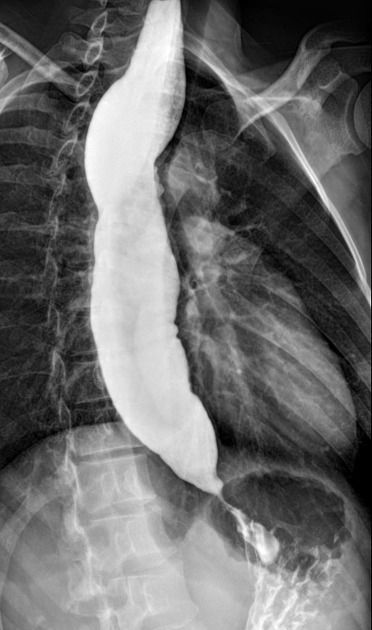

Achalasia is an esophageal motility disorder characterised by 3 major abnormalities: failure of the lower esophageal sphincter to relax with swallowing, loss of peristalsis in the distal two-thirds of the esophagus and increased resting tone of the lower esophageal sphincter. The exact cause of achalasia is poorly understood. Some researchers suspect it may be caused by a loss of nerve cells in the esophagus. The clinical presentation includes dysphagia for both solids and liquids, weight loss, nocturnal cough and regurgitation. The confirmed diagnosis is made by esophageal manometry and by doing an X-ray of the upper digestive system after the patient has swallowed a barium pill. The barium swallow shows esophageal dilatation with uniform tapering of the distal esophagus and this is know as the "Bird's beak appearance" as shown in the picture above. Achalasia treatment focuses on relaxing or stretching open the lower esophageal sphincter so that food and liquid can move more easily through the digestive tract. The nonsurgical treatment options include pneumatic dilation and the use of muscle relaxants such as calcium channel blockers (nifedipine), nitrates or injecting the botulinum toxin into the LES. The surgical options include performing the Heller's myotomy or a peroral endoscopic myotomy.